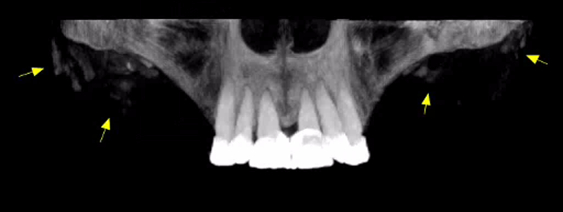

Συχνά σε εξετάσεις Οδοντιατρικής Υπολογιστικής Τομογραφίας (CBCT) παρατηρούμε υπέρπυκνες δομές οι οποίες βρίσκονται στα μαλακά μόρια και επί τα εκτός των γνάθων, που η εικόνα τους δεν παραπέμπει σε κάποια γνωστή παθολογία της τραχηλοπροσωπικής χώρας.

Σε όλες τις προηγούμενες περιπτώσεις οι παρατηρούμενες υπέρπυκνες δομές δεν είναι τίποτε άλλο παρά υλικά αισθητικών επεμβάσεων!

Απεικονιστικά παρατηρούνται πολλαπλές συρρέουσες υπέρπυκνες δομές μικρών διαστάσεων εντός των μαλακών μορίων και πλησίον του εξωτερικού τους περιγράμματος.